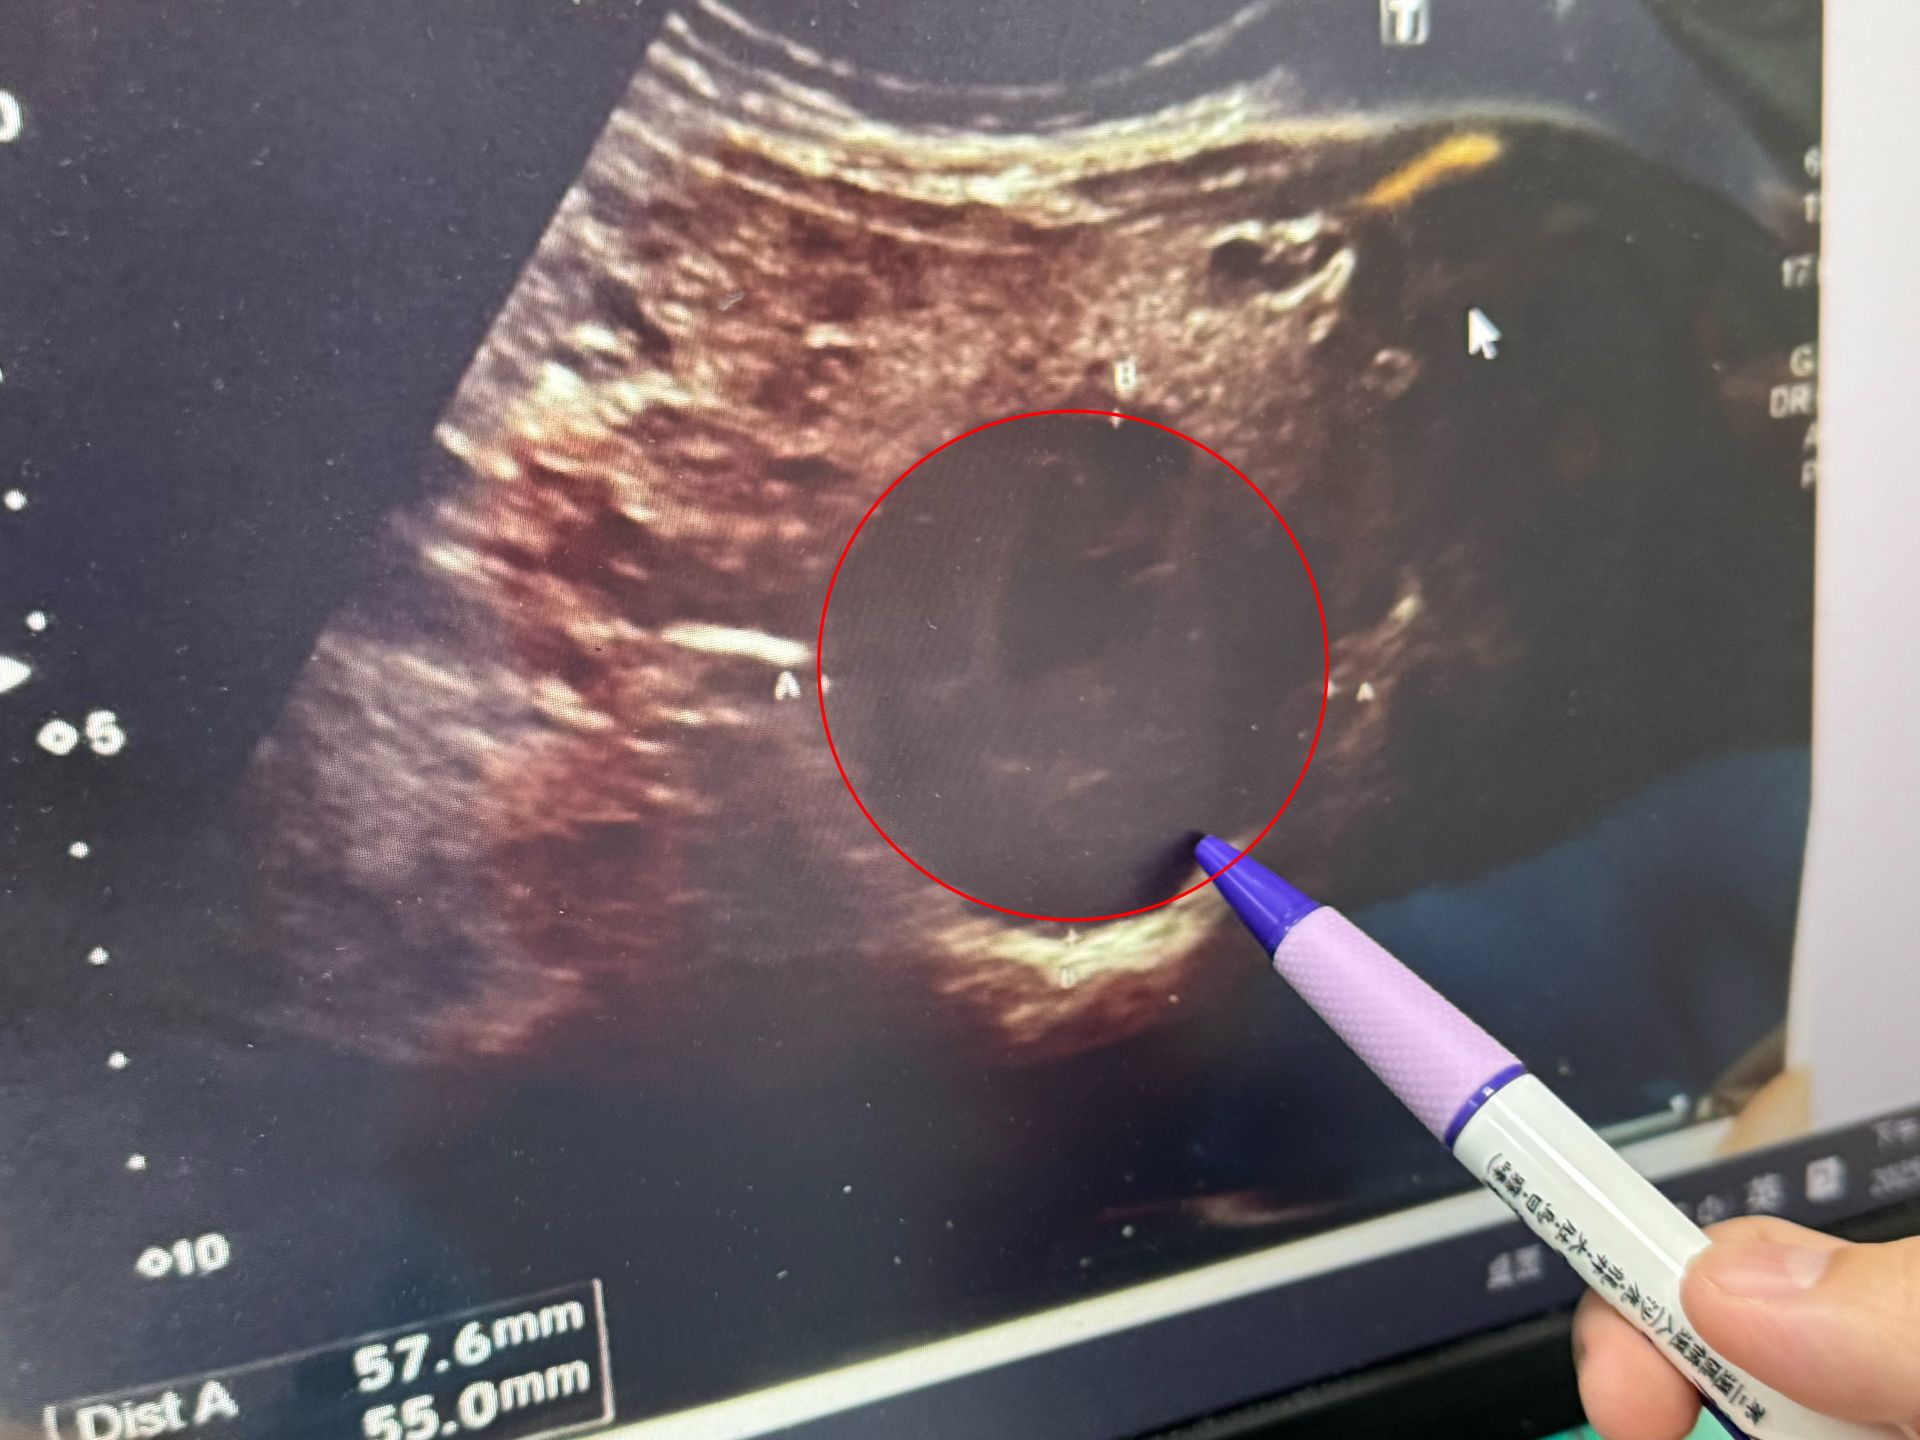

駐診在李綜合醫院的臺中榮總外科主治醫師吳坤達表示,患者被診斷出肝癌後,長期在他院接受治療肝癌栓塞治療,日前到診間時透露,他腹部非常痛,希望能採取其他的治療,因此,幫患者進一步檢查評估後,除了確認肝癌腫瘤大小,同時發現腎臟出現腎衰竭的徵狀,與患者討論後,決定採用韓國類機械手臂手術器進行微創手術切除肝臟。